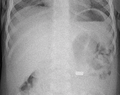

AP X ray showing a 9mm battery in the intestines

Lateral X ray showing a 9mm battery in the intestines